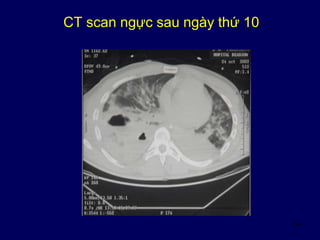

CT scan ngực sau ngày thứ 10

Sau ngày thứ 10

• Sốt 39°C

• Bạch cầu 30 000 / mm3

• Đặt NKQ, thở máy,

• PEEP 8, áp lực cao nguyên 35 cmH2O

• PaO2 / FiO2 < 150

• Cần bù dịch

Sau ngày thứ 10: bội nhiễm dịch màng phổi

• Điều trị

– Kháng sinh

– Bảo vệ phổi bên kia không bị khạc ộc mủ sang

– Dẫm lưu qua da dưới CTscan

hoặc

– Phẫu thuật: cắt thùy phổi